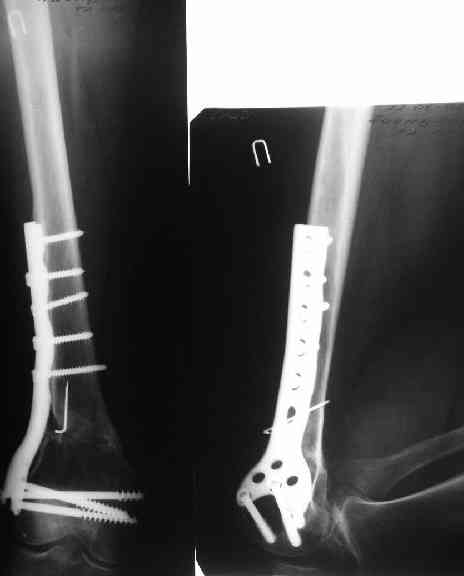

В приложении как раз видна эволюция использововшихся у нас большеберцовых гвоздей. Первый - дизайн как у UTN, второй - разнесены 45 градусные отверстия (зачем их вообще изначально так нелепо на одном уровне сделалм???), третий - убрано сиавшее лишним статическое отверстие, Herzog's bend перемещен более проксимально.